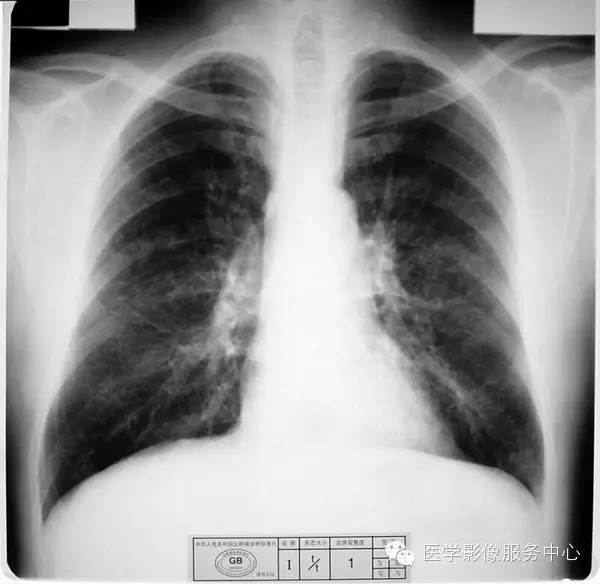

4.2 一期尘肺(Ⅰ)

a)Ⅰ:有总体密集度1级的小阴影,分布范围至少达到两个肺区。

b)Ⅰ :有总体密集度1级的小阴影,分布范围超过4个肺区或有总体密集度2级的小阴影,分布范围达到4个肺区。